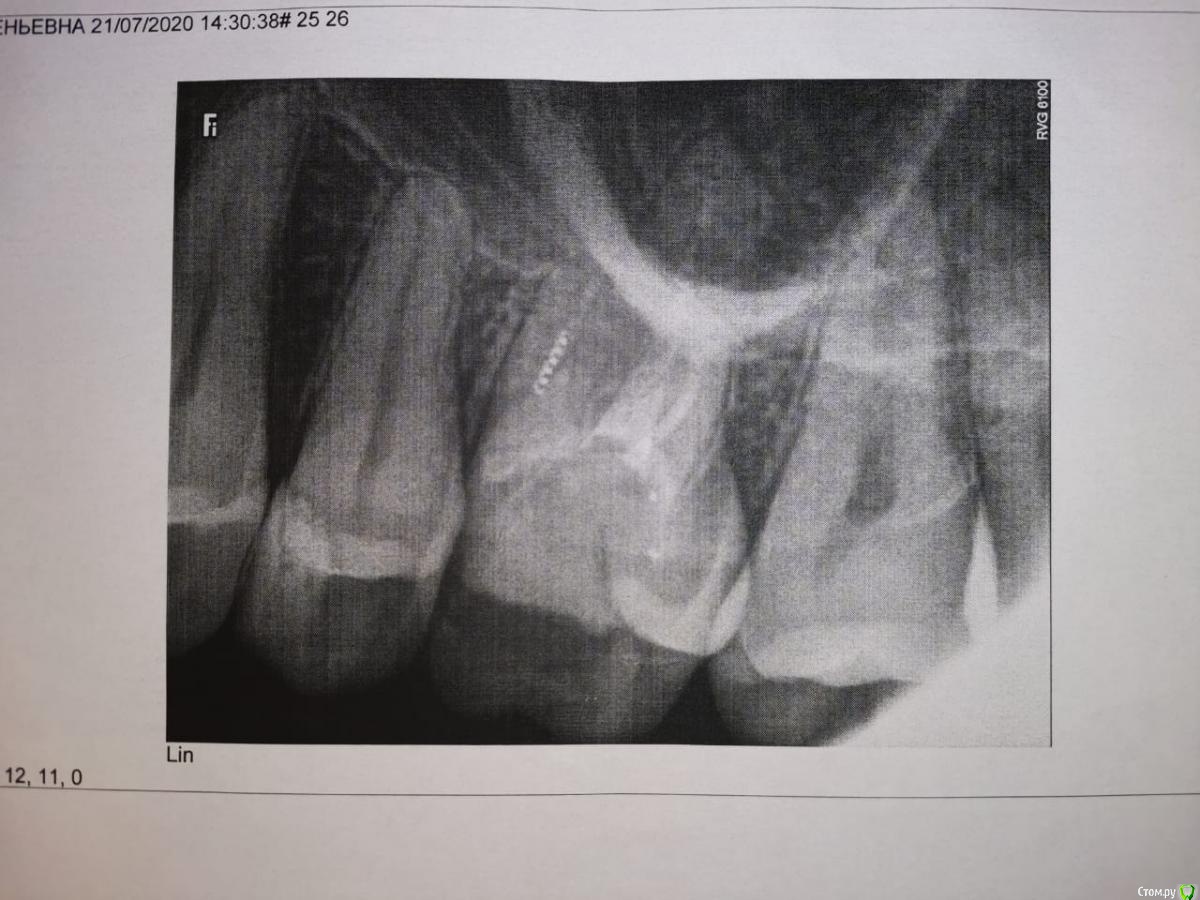

Здравствуйте. Лет 17 назад мне удалили нерв в верхней шестерке слева, оставив фрагмент инструмента. Пару дней назад об этом узнала. Хотела сходить к эндодонтисту, чтобы под микроскопом извлек, но присмотрелась и увидела, что зуб как будто треснул вдоль (вертикально). Видно с внешней и внутренней стороны. Теперь волнует, можно ли его сохранить или придется вырывать и ставить имплант?